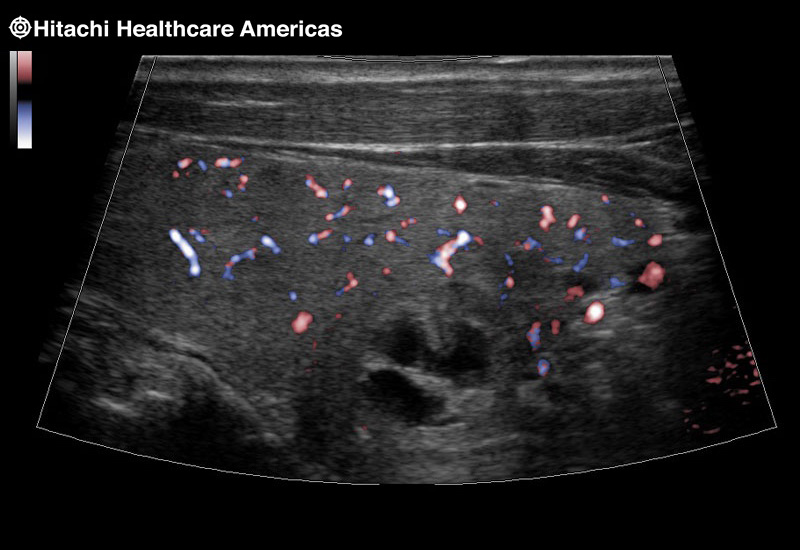

Superior guidance for all applications

Fujifilm Healthcare Americas is committed to designing tools that help surgeons navigate inside the human body and provide the necessary information to immediately make critical surgical decisions.

Fujifilm Healthcare's dedication to Surgeons provides outstanding ultrasound technology, professional support and the specialized tools necessary to best perform comprehensive real-time ultrasound imaging in Breast Surgery, General Surgery, Laparoscopic Surgery, Neurosurgery, Robotic Surgery and Surgical Oncology.